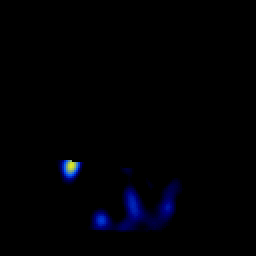

overlay -- Slice #5

[Home][Help][Clinical] Slice 5

Click on sagittal image to select slice. Click on thin tickmark to change timepoint, or thick tickmark for overlay.